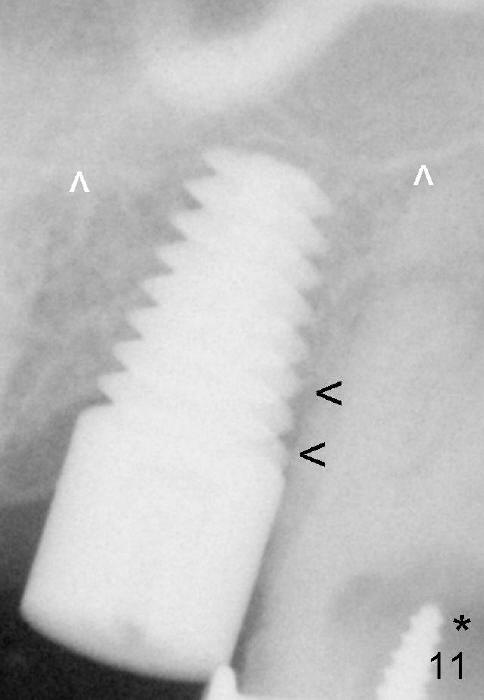

Fig.11: In fact the implant has penetrated the sinus floor (white arrrowheads); *: caries of the 3rd molar; black arrowheads: exposed distal threads.